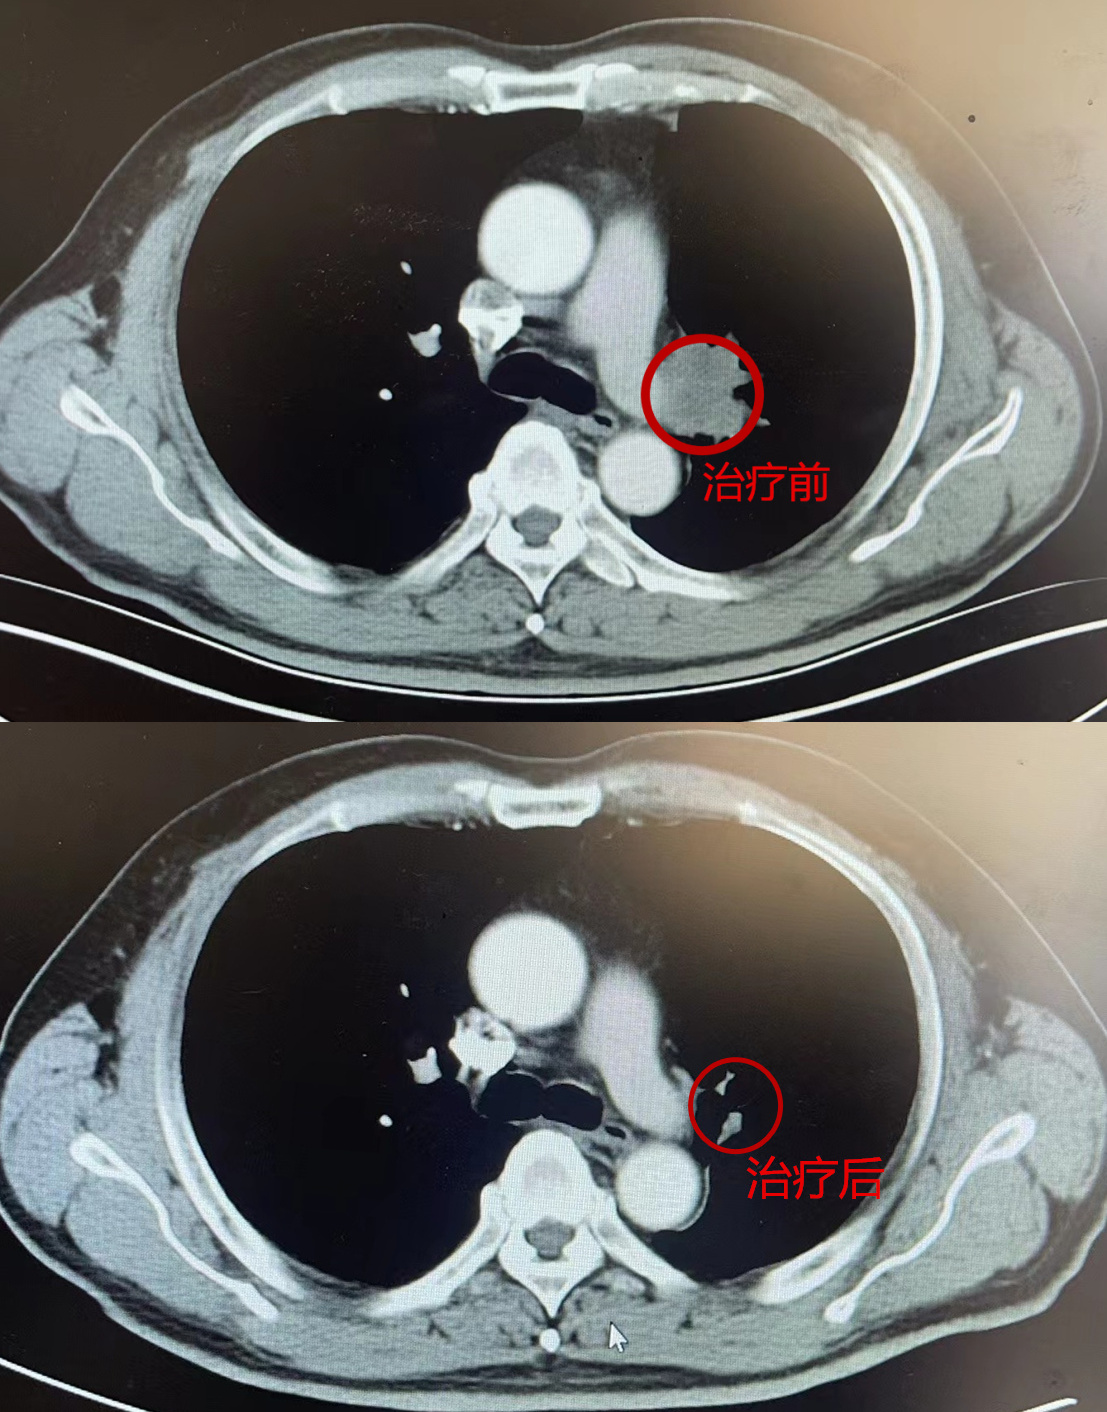

经3个周期“化免攻击”,老伯的肿块比原来缩小了90%以上,胸部CT上几乎看不见肿瘤!

紧接着,外科接棒。肿瘤科罗清泉主任团队为老人施行了左肺上叶切除术,完整摘除了肺部肿块。

更令人惊喜的是,术后病理显示,老伯肺内已没有任何肿瘤细胞,达到了病理完全缓解!